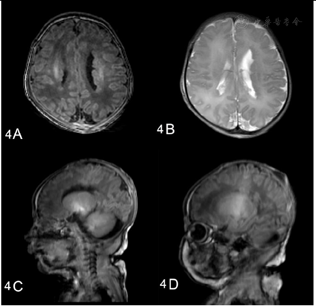

患儿辅助检查提示多系统异常。头颅磁共振成像显示双侧脑室周围结节性异位和大枕大池(图4)。胸部X光显示心影逐渐扩大,同时伴有双肺渗出增多,腹部X光显示肠管扩张,伴发多个气液平面(图5)。超声心动图显示心功能不全、房间隔缺损、动脉导管未闭、二尖瓣发育不良和主动脉扩张。泌尿超声检查发现肾积水。脑干听觉诱发电位显示双耳听通路明显延迟。血液生化检查提示肝酶、心肌酶、B型脑钠肽升高,严重的低钠低氯性碱中毒同时合并低钾血症。新生儿期甲状腺功能检测显示总T4(total T4, TT4)93.40 nmoL/L↓(正常:105.5~208.5 nmoL/L),促甲状腺素(thyroid stimulating hormone,TSH)18.58 uIU/ml↑(正常:0.66~6.29 uIU/ml)。随访过程中发现患儿出现严重的甲状腺功能减退,TT4显著降低(TT4 29.00 nmoL/L),TSH显著升高(>150 uIU/ml)。甲状腺超声显示甲状腺大小正常。